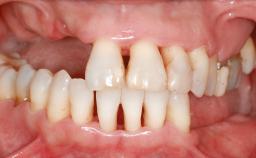

An 18-year-old man was referred for implant therapy in the posterior mandible to the Department of Oral Surgery and Stomatology (University of Bern, Switzerland). He was healthy and did not smoke. Tooth 35 was congenitally missing, involving a single-tooth edentulous space that offered an adequate mesiodistal dimension for implant placement but exhibited a typical pattern of buccal flattening. A panoramic radiograph was obtained, which revealed a sufficient vertical bone height above the mandibular canal and a normal bone structure in the edentulous area.